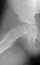

The frog-leg lateral view of the right hip demonstrated an obvious grade

1 slipped capital femoral epiphysis

.